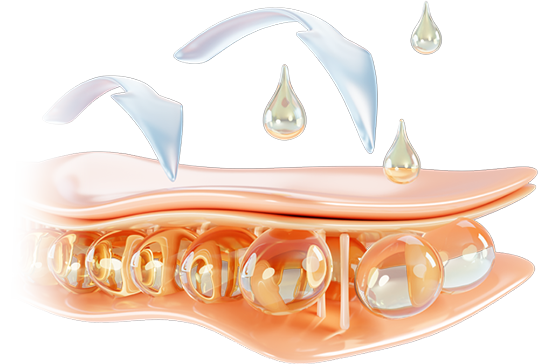

콜라겐 구조의 70%

클로인,프롤린,라이신은 콜라겐의 70%를 차지합니다.

섬유아세포가 대사활동을 하는 동안 섬유아세포에 자극을 주어

콜라겐을 생성하거나, 콜라겐이 서로 합성되는 현상이 일어납니다.

섬유아세포가 대사활동을 하는 동안 섬유아세포에 자극을 주어

콜라겐을 생성하거나, 콜라겐이 서로 합성되는 현상이 일어납니다.